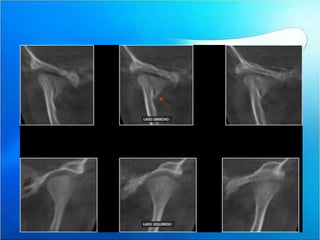

Spiessl y schroll 1972

•   Tipo :

•   I =sin desplazamiento

•   II=Baja con desplazamiento

•   III=alta con dezplasamiento

•   IV= baja con dislocacion

•   VI =fractura condilar intracapsular

Paciente femenino 3 años de edad es referida a la consulta para la evaluación

de la articulación témporo-mandibular, con antecedente de traumatismo en

la zona sinfisiaria debido a caída.

Se le realiza el estudio con tomografía volumétrica